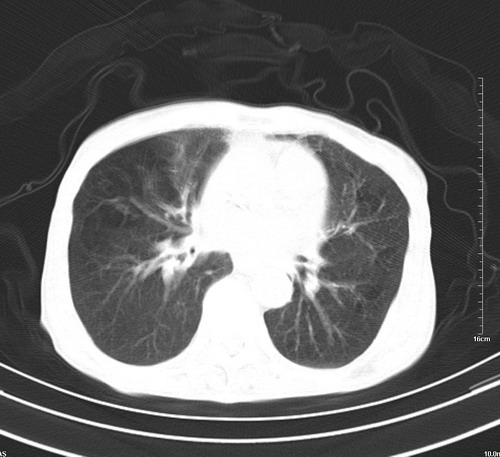

中后纵隔占位,气管、食道受压、变形、移位。恶性可能性大。

考虑:中后纵隔转移瘤可能性大,主动脉硬化。

中后纵隔占位, 考虑:转移瘤不除外.

1 气管旁、隆突下淋巴结明显肿大,肝左叶外侧段低密影,都考虑转移。

纵隔淋巴结肿大,考虑转移而来

肺癌,纵隔淋巴结转移,肝左叶病变考虑为转移病灶。

中后纵隔转移瘤可能性大,主动脉硬化。

后中纵隔团块影,伴气管、食道受压移位,首先考虑转移瘤,肝s5段低密度灶。建议增强检查,另外其结肠是否有问题请提供,右肺部分肺叶局限含气增多,考虑局限肺气肿。

建议强化检查,考虑纵隔型肺癌,小细胞可能性大。

后中纵隔淋巴结肿大,首先考虑转移瘤。